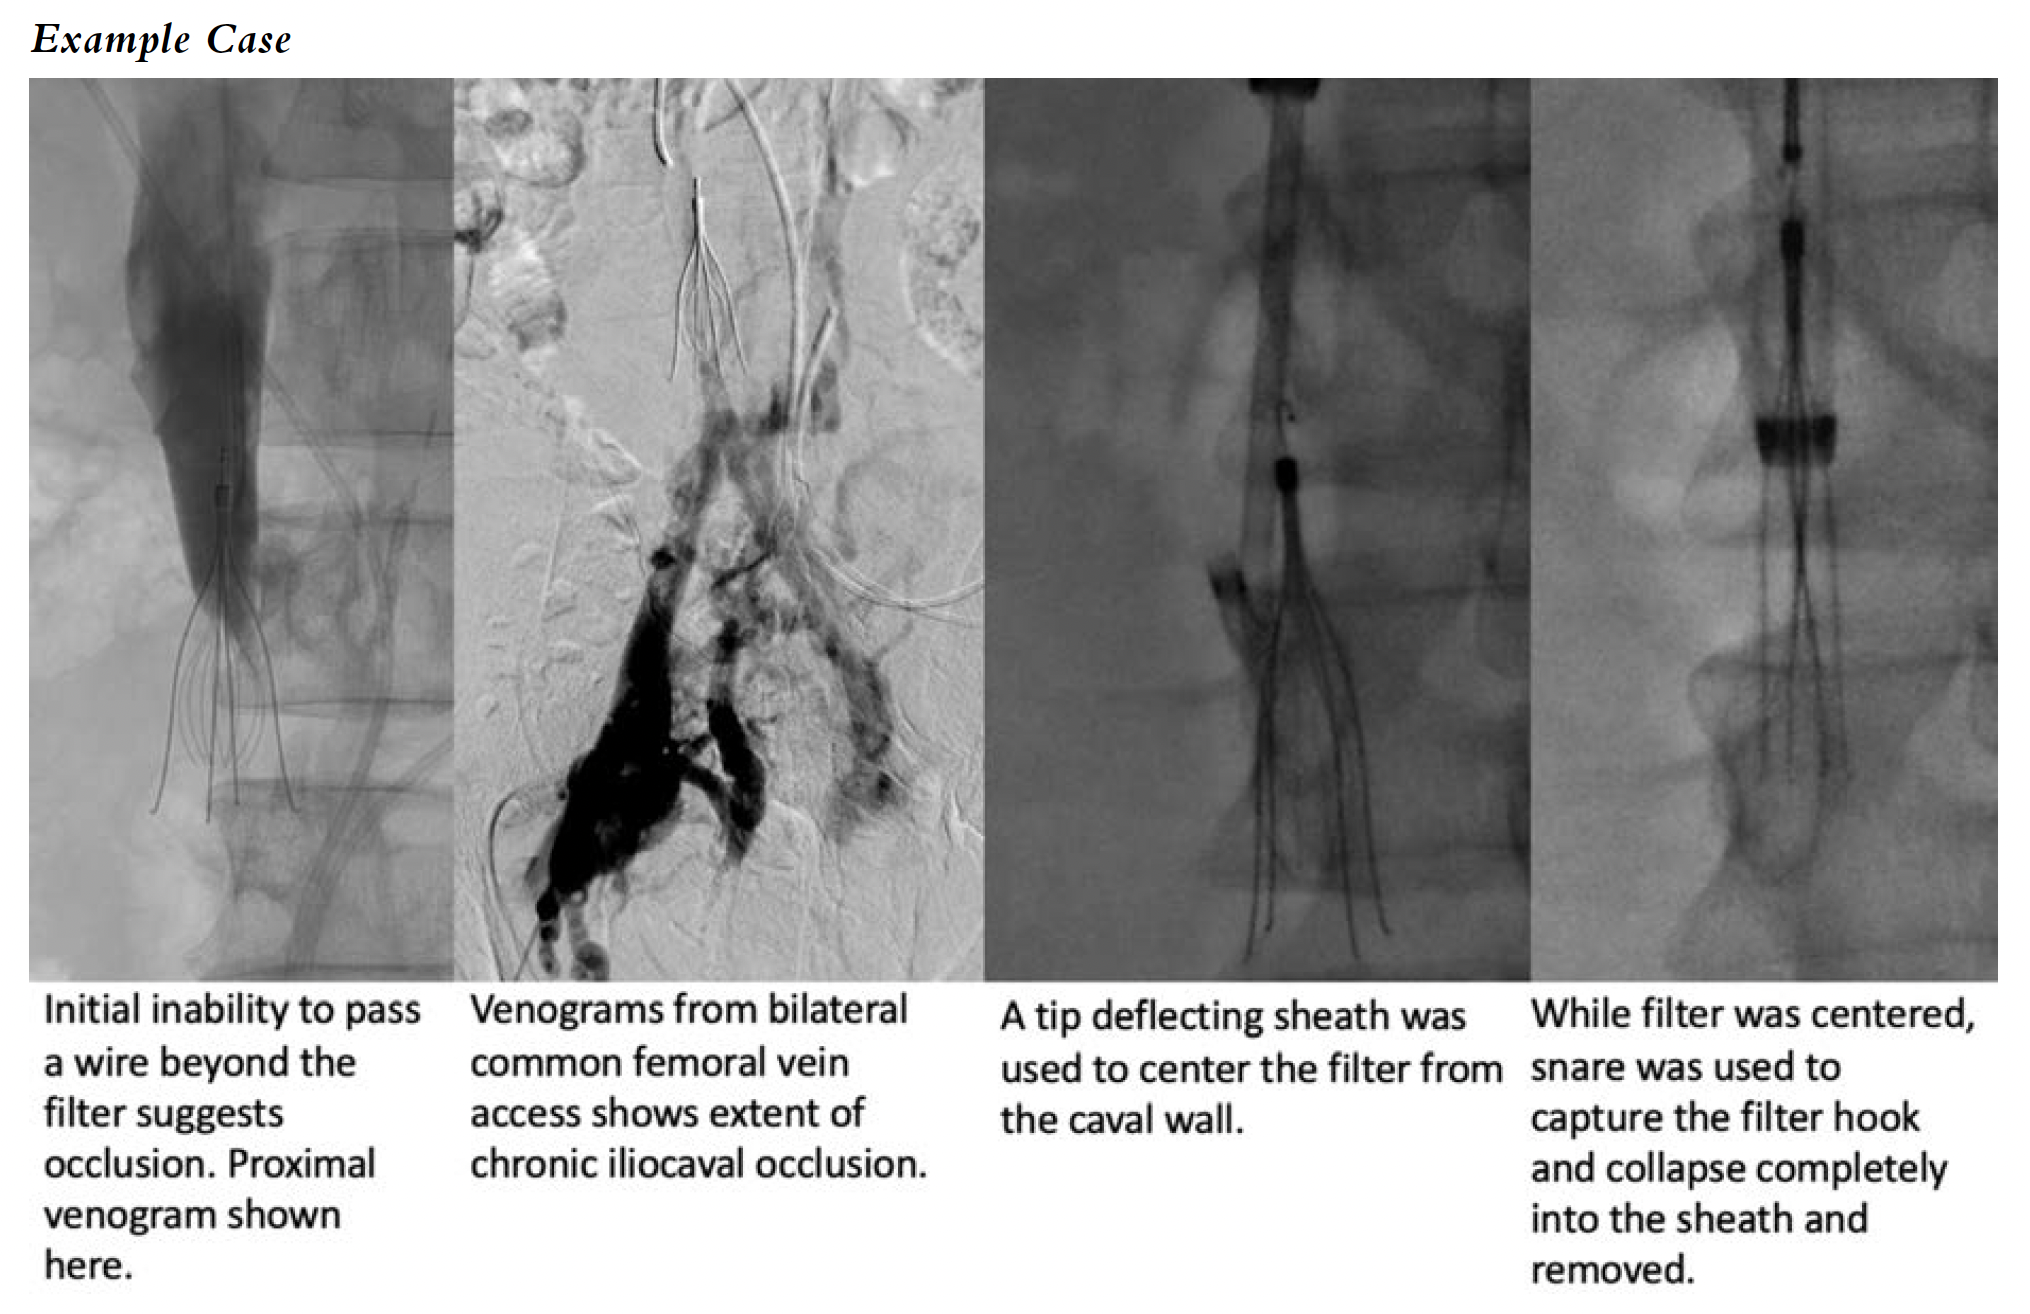

Complex IVC Filter Removal With Iliocaval Occlusion

As described above, a well-known complication of long-term indwelling IVC filters is thrombosis of the venous system and possibly chronic occlusion. This can be a very complex situation as the decision has to be made whether to attempt a complex IVC filter removal and iliocaval reconstruction. This should be a carefully assessed approach. Once chronically occluded, it may be prudent to leave the filter in place and not pursue reconstruction if the patient is not symptomatic, as they may have collateralized sufficiently and may be able to tolerate mild symptoms such as minimal swelling. However, patients with such situations can be found to have post-thrombotic syndromes; these are especially troubling for patients with nonhealing or recurrent venous ulcers of the lower extremities, which can be debilitating and often take months to years of wound care and have other complications. Other indications may include venous claudication, symptomatic varicose veins, etc. If the intervention is undertaken, the decision also includes whether to perform exhaustive attempts to remove the embedded IVC filter, to potentially stent through and exclude the filter. There are no definitive data regarding which method provides the best outcome; however, we feel that if the filter can be removed, it should be, and this may reduce issues with pushing the filter against the caval wall (conical filters) by the stent scaffolds, which may cause additional caval perforation and symptomatic irritation of adjacent structures. If the proximal and/or distal aspect of the filter can be controlled, we feel it should be removed. If extracaval or in some instances with the polyhedral filters, it may be easier to stent through the filter. Regardless of approach, good preoperative cross-sectional imaging, frank discussions with patient/family and referrers, and access and experience with advanced techniques are recommended.

Example Case of Iliocaval Occlusion with IVC Filter

The patient is a septuagenarian male with a history of stroke and an incidentally found IVC filter, which he was not aware of 12 years earlier when he was being worked up for abdominal pain and lower extremity venous ulcers. The patient had a CT scan, which showed iliocaval occlusion with collateral formation, and he was planned for intervention. Post procedure, the patient experienced improvement of abdominal pain and eventual wound healing of the lower extremity. His venous insufficiency has been managed lifelong with compression therapy and other conservative measures.